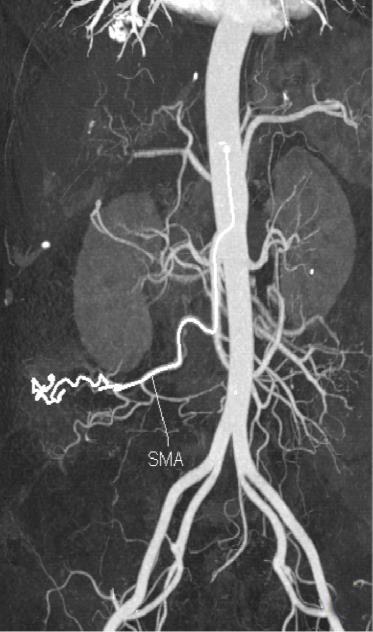

• 计算机体层摄影血管造影在腹腔镜结肠癌根治术前评估中的应用效果

2025, 31(6):24-31. DOI: 10.12235/E20240177

摘要 (181) HTML (147) PDF 4.65 M (171) 评论 (0) 收藏

摘要:目的 分析计算机体层摄影血管造影(CTA)在腹腔镜结肠癌根治术前评估中的应用效果。方法 回顾性分析2021年1月-2024年2月于该院接受腹腔镜结肠癌根治术的120例患者的临床资料。其中,60例行常规腹部CT和CTA,60例行磁共振成像(MRI)。以术后病理为金标准,判断CTA对临床T分期与术后病理的一致性,以及评估肿瘤是否侵犯肠系膜血管和周围组织的准确度。结果 术前CTA诊断T分期的准确率为95.00%(57/60),一致性好(Kappa = 0.925,P < 0.05);术前MRI诊断结肠癌T分期的准确率为98.33%(59/60),两者比较,差异无统计学意义(χ2 = 0.26,P > 0.05)。CTA预判肿瘤是否累及肠系膜上动脉、肠系膜上静脉、肠系膜下动脉、肠系膜下静脉、腹主动脉、肾动脉、肾静脉和脾动脉等血管,与术后病理的一致性好。特别是在预测肠系膜血管受累方面,CTA的敏感度为94.44%,特异度为95.83%,准确度高达95.00%。结论 对于行腹腔镜结肠癌根治术的患者,术前CTA不仅能清晰地显示结肠癌T分期,还能揭示肠系膜血管的走行和变异,以及肿瘤与周围组织的关系和侵犯程度,从而为手术规划提供强有力的支持,确保了腹腔镜手术的安全性,减少了不必要的手术风险。